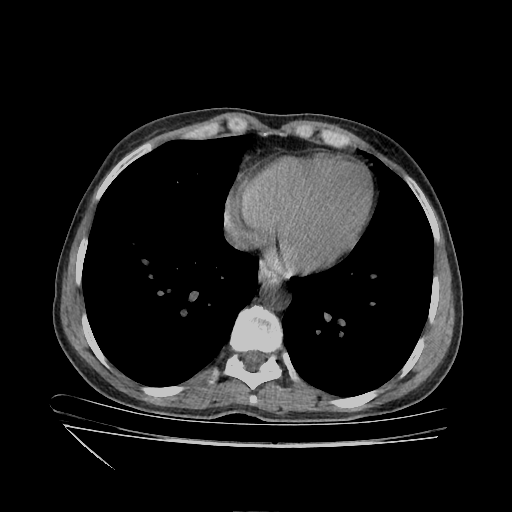

Original VENOUS CT scan

No window - Raw intensity values

Lung window (WL -600, WW 1500 β†’ Low βˆ’1350, High +150)

Mediastinum window (WL 40, WW 400 β†’ Low βˆ’160, High +240)